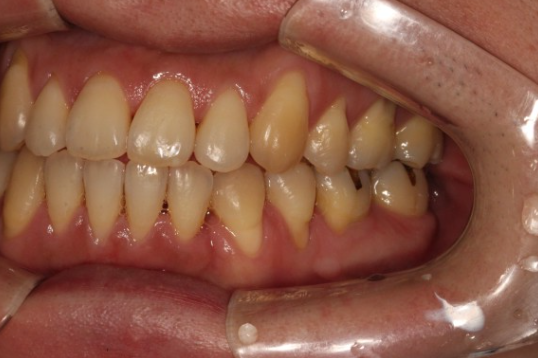

2.부정교합 (치아의 물림 이상)

치아의 가장 중요한 기능은 씹는 것입니다. 치아에게 중요한 것은 외적인 아름다움이 아닌 음식물을 잘 부수는 것입니다. 사람의 치아는 종종 윗니와 아랫니가 잘 물리지 않게 되는 부정교합으로 자랍니다. 이 경우 치아가 음식을 잘 부술 수 있도록 턱이 편안한 방향으로 이동하게 됩니다.

즉 치아사 비뚤 하게 나면, 우리는 본능적으로 음식을 잘 씹기 위해 턱을 틀어 음식을 먹게 됩니다. 이러한 상황이 지속적으로 나타난다면 당신은 얼굴이 틀어짐을 느끼게 됩니다.